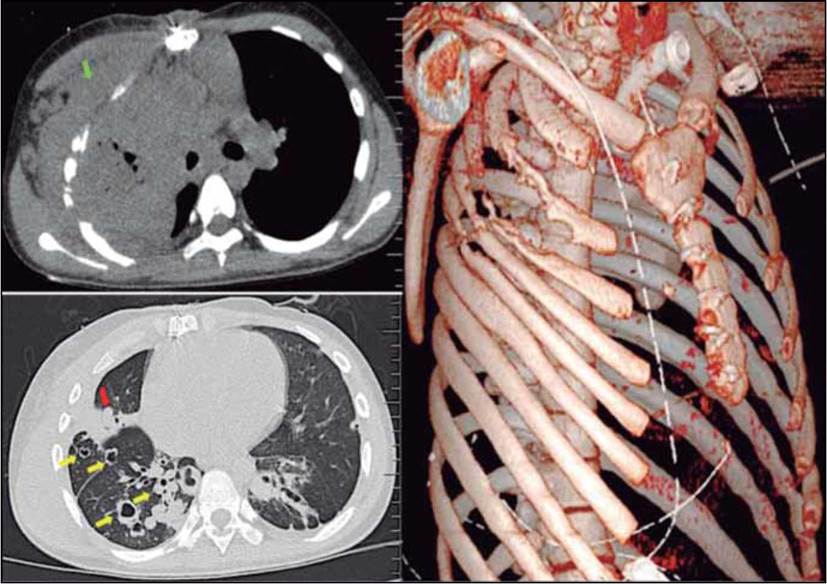

Debido al cuadro clínico de neumonía a repetición debió recibir múltiples esquemas antibióticos, con última hospitalización en diciembre de 2017 con tratamiento antibiótico con vancomicina y cefepima. Debido a que no se presentaba mejoría clínica, en enero de 2017 se realizó fibrobroncoscopia y nasofibrolaringoscopia para determinar si había mayor crecimiento de las lesiones papilomatosas que estuvieran empeorando el pronóstico del paciente y pudieran ser tributarias de nueva corrección quirúrgica, se evidenció que dichas lesiones generaban obstrucción significativa de la tráquea (50%), se tomaron biopsias cuyos cultivos reportaron actinomicetos sensibles exclusivamente a quinolonas y sulfas. Posteriormente se evidenció formación de fístula en pared anterior de tórax por lo que se decidió realizar imágenes por tomografía en las que se evidenciaron múltiples consolidaciones y bronquiectasias generalizadas predominantemente en lóbulo superior derecho, con extensión a pared torácica (EN) y osteomielitis en 2-3-4-5 arcos costales derechos; cultivos de la secreción de la pared torácica reportaron Klebsiella pneumoniae, con presencia de betalactamasas tipo Amp C por antibiograma. En la Figura 1 se observan algunos de los hallazgos radiológicos más destacados.

El paciente fue llevado a cirugía el 4 de abril de 2017, donde se confirma empiema at necessitatis con osteomielitis de arcos costales 2-3-4-5 derivado de infección pulmonar extensa, múltiples papilomas en pulmón, destrucción de lóbulo superior pulmonar con absceso y fístula a pared anterior de tórax por lo que realizan neumonectomía radical derecha en intento de controlar la infección. Se planeó resección de arcos costales y toracoplastia en un segundo momento quirúrgico y se tomaron nuevos cultivos. Microbiología reportó el crecimiento de Pseudomonas stutzeri, Staphylococcus aureus meticilinorresistente con patrón hospitalario, Scopulariopsis brevicaulis y Klebsiella oxytoca panresistente por lo que se cambia manejo antibiótico a anfotericina B deoxicolato, meropenem, tigeciclina y polimixina B.